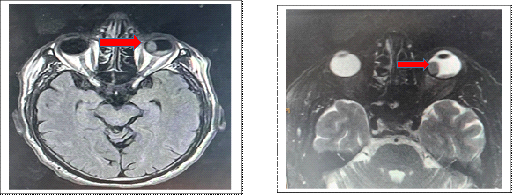

Imaging was complemented by orbitocerebral MRI, which revealed a suspicious mass in hyposignal T1 and hypersignal T2, with gadolinium uptake, suggesting in the first instance a choroidal melanoma to be correlated with anatomopathological data. The patient's extension work-up at the diagnostic was negative (cerebral, lung and hepatic scan) (Figure 1).

Figure 1 Intraocular mass with T1 hypersignal and T2 hypersignal on the nasal side.

Very suggestive of choroidal melanoma